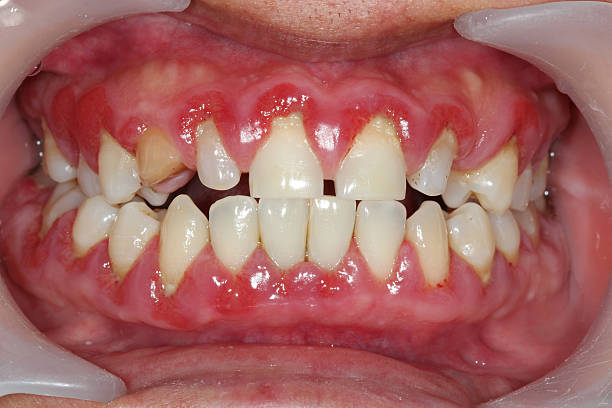

Gingivitis: A non-destructive form of periodontal disease characterized by inflammation of the gingiva (gums), often caused by plaque accumulation. Clinically, it presents as redness, swelling, and bleeding on probing. In images, gingivitis can be recognized by the erythematous and edematous appearance of the gum margins (Fig. 1(c)).

(c) Gingivitis